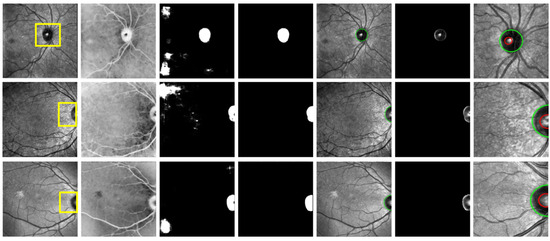

2.2.1. Anatomical Segmentation

Pre-Processing

Optic Disc Candidates

Post Processing

- In order to eliminate noise pixels situated between the candidates, particularly in low-quality IR-SLO images exhibiting intensity variations despite applying the histogram matching method, morphological closing and opening operations, using a structural element in the shape of an ellipse, were performed on the binary images containing the candidates.

- Since the optic disc appears as bright areas in the inverted images that are generated during the pre-processing phase, dark regions cannot be identified as the optic disc. To filter out candidate areas with a low probability of being the optic disc, candidates with a mean intensity lower than a specific threshold were excluded. This threshold was determined based on the mean intensity values of all candidates in each image.

- Candidate regions in each image with an area smaller than a certain threshold were excluded (2300 pixels for candidates located on either side of the images and 3000 pixels for those located near the center of the images).

- The shape and area of the remained candidates were determined using connected component analysis, and those with a line shape or a low width-to-length ratio in their bounding box were eliminated. Candidate regions close to the center of the images were further filtered by removing those with a low length-to-width ratio within their bounding box. Ultimately, the final optic disc candidate was identified as the one with the greatest area.

- The final optic disc candidate underwent a blob detection algorithm to delineate the boundary of the optic disc. To achieve this, an ellipse transform was employed, considering that in some images only one arc of the optic disc may be visible. The algorithm used to calculate the boundary and width of the optic disc candidate positioned on the sides of the IR-SLO images is summarized in the Supplementary Figures S3 and S4.

Cup Segmentation

- The bounding box of the candidate should entirely fall within the optic disc boundary.

- The width-to-length or length-to-width ratio of the candidate must be less than 2, as the cup does not have a narrow oval shape.

- The area of the candidate must exceed a specific threshold, set at 700 in this work.

Vessel Segmentation

Binary Vessel Segmentation Map